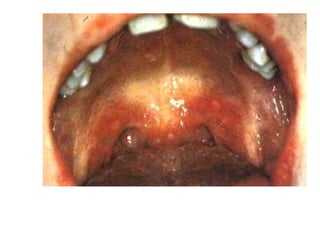

Herpangina:

There is an abrupt onset of fever, sore throat,

anorexia, dysphagia, vomiting, or abdominal

pain. The pharynx is usually hyperaemic, and

characteristic discrete vesicles occur on the

anterior pillars of the fauces, the palate,

uvula, tonsils, or tongue. The illness is self-

limited and most frequent in small children.

• #28 Герпангіна, Коксаки-А